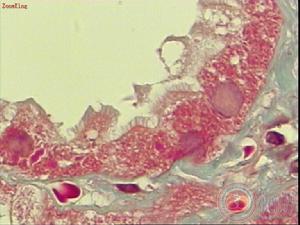

1、腎小管損傷

腎缺血或腎中毒時引起腎小管急性嚴重的損傷,小管上皮細胞變性、壞死和脫落、腎小管基膜斷裂,一方面脫落的上皮細胞引起腎小管堵塞,造成管內壓升高和小管擴張,致使腎小球有效濾過壓降低和少尿,另一方面,腎小管上皮細胞受損引起腎小管液回漏,導致腎間質水腫。

腎小管損傷細胞 腎缺血和腎毒素能使腎素—血管緊張素系統活化,腎素和血管緊張素Ⅱ分泌增多、兒茶酚胺大量釋放、TXA2/PGI2比例增加,以及內皮素水平升高,均可導致腎血管持續收縮和腎小球進球動脈痙攣,引起腎缺血缺氧,腎小球毛細血管內皮細胞腫脹致使毛細血管腔變窄,腎血流量減少,GFR降低而導致急性腎衰竭。